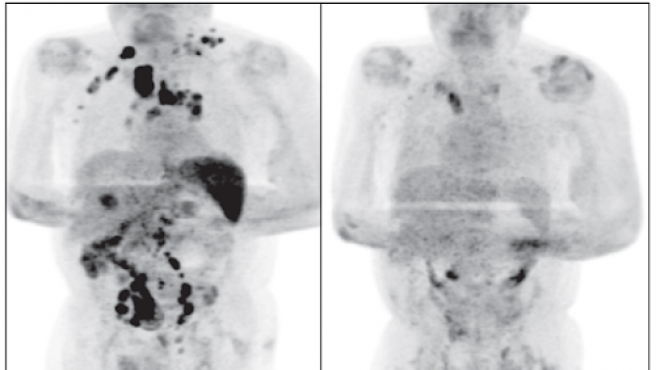

El caso, que fue publicado en la revista British Journal of Haemathology, corresponde a un hombre de 61 años que desarrolló una respuesta antitumoral que le ayudó a remitir parcialmente el linfoma de Hodgkin que sufría.

De acuerdo con el reporte, el hombre estaba en el estado III de gravedad, es decir, que su cáncer se encontraba bastante extendido por el cuerpo abarcando áreas de ganglios linfáticos a ambos lados del diafragma, tanto arriba como abajo del diafragma.

La sorpresa de los médicos que lo trataron se dió cuatro meses después cuando el paciente regresó a consulta médica y los ganglios inflamados habían disminuido de forma drástica. Los científicos creen que la infección por SARS-CoV-2 desencadenó una respuesta inmunitaria y terminó ayudando a que su cuerpo combatiera el cáncer.